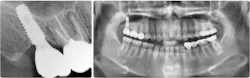

Hydraulic sinus lifting is a technological leap forward in sinus lift procedures. These innovative devices utilize hydraulic pressure to lift the sinus membrane gently and precisely, creating sufficient space for implant placement without the need for excessive bone manipulation (figure 3).

Hydraulic lifts can effectively prevent many of the aforementioned complications. Membrane perforations and injury to nearby vital structures are minimized because of the use of millimeter-precise drill stoppers, as well as simply using saline instead of blunt instruments to separate the thin sinus membrane. The flat-ended drills and stoppers in hydraulic techniques eliminate much of the guesswork involved in drilling to breach the sinus.

There is no manual bone manipulation, meaning hydraulics are less invasive and therefore promote faster healing for patients. Because mallets are not used, the patient experiences less trauma and doesn’t suffer related side effects such as tinnitus or concussions. Most importantly, unlike traditional methods that involve manual force, hydraulic lifts offer controlled and predictable elevation of the sinus floor, minimizing trauma to surrounding tissues and reducing postoperative complications.

As the landscape of implantology evolves, the adoption of hydraulic lifts is poised to become the gold standard in noninvasive sinus lift surgeries, reshaping the future of dental implant procedures (figures 4–11).